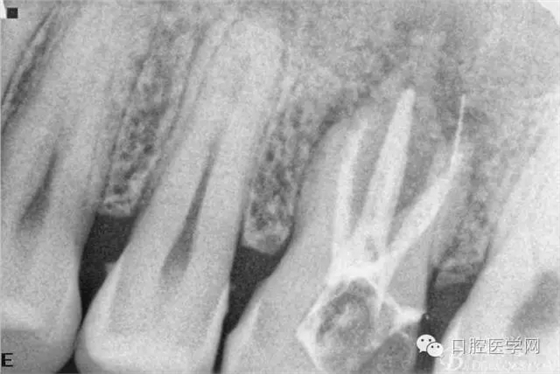

檢查26Ⅲ°松動(dòng)(頰舌向、近遠(yuǎn)中向、頜齦向)。X線片顯示根尖周彌漫性炎性陰影。

初診X線片

擴(kuò)根片(可惜遠(yuǎn)頰根有一斷針)